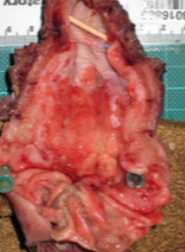

55yo male presents with persistent, vague epigastric pain for many months. Associated with this is nausea and weight loss. He has a history of H. pylori infection

Stomach cancer (adenocarcinoma shown)